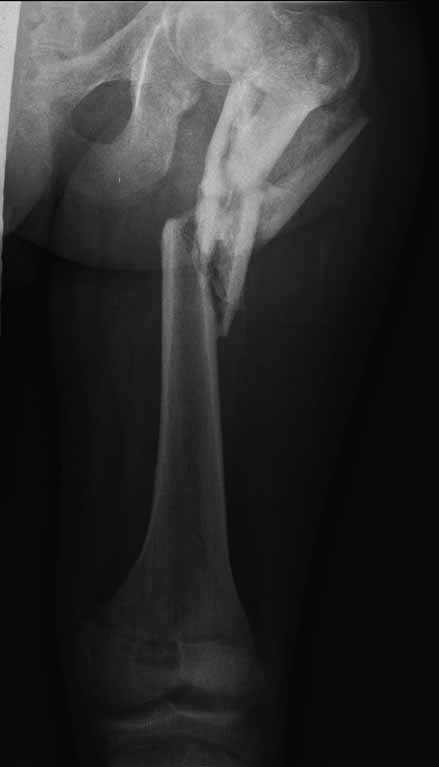

Пациенту 22 года. Травма в июле 2010г, лечился в районной больнице. К нам попал в апреле 2011г.Тяжелая сочетанная травма (29.07.2010): тупая травма живота с повреждением внутренних органов. Закрытая травма грудной клетки с переломом ребер. Пневмоторакс справа. Тяжёлая позвоночно-спинномозговая травма. Закрытый осложнённый переломо-вывих С5 позвонка. Верхний парапарез, нижняя параплегия, нарушение функции тазовых органов по типу недержания. Цекостома. Пролежень левой ягодичной области. Неправильно консолидированные переломы верхних третей обеих бедер. Застарелый вывих левого бедра.Осложнение: Поддиафрагамльный абсесс слева, забрюшинного пространства. Свищ желудка и ободочной кишки. Синегнойный сепсис. Двухстороняя пневмония. Но это уже анамнез.Пациент был неоднократно оперирован на органах брюшной полости и осложнениями с ними связанными.

В ягодичной области слева глубокий пролежень размером 2х2см, дном является вывихнутая головка бедра. Неврологически в нижних конечностях динамика положительная, появились движения в правой стопе, чувствительность в стопах.По переломам бедер: подвижности в местах переломов нет, снимки высылаю.

Уважаемые коллеги, помогите определиться с оптимальной тактикой в лечении перелома бедер. Степень оснащенности у нас достаточная (аппараты, штифты, пластины, ЭОП).

Планирую начать с правого бедра, ЧКО таза (передняя рама) с фиксацией бедра. О/клазия места перелома правого бедра и устранение грубых смещений в аппарате. окончательно можно оставить и в аппарате. Далее аппаратное устранение вывиха левого бедра.